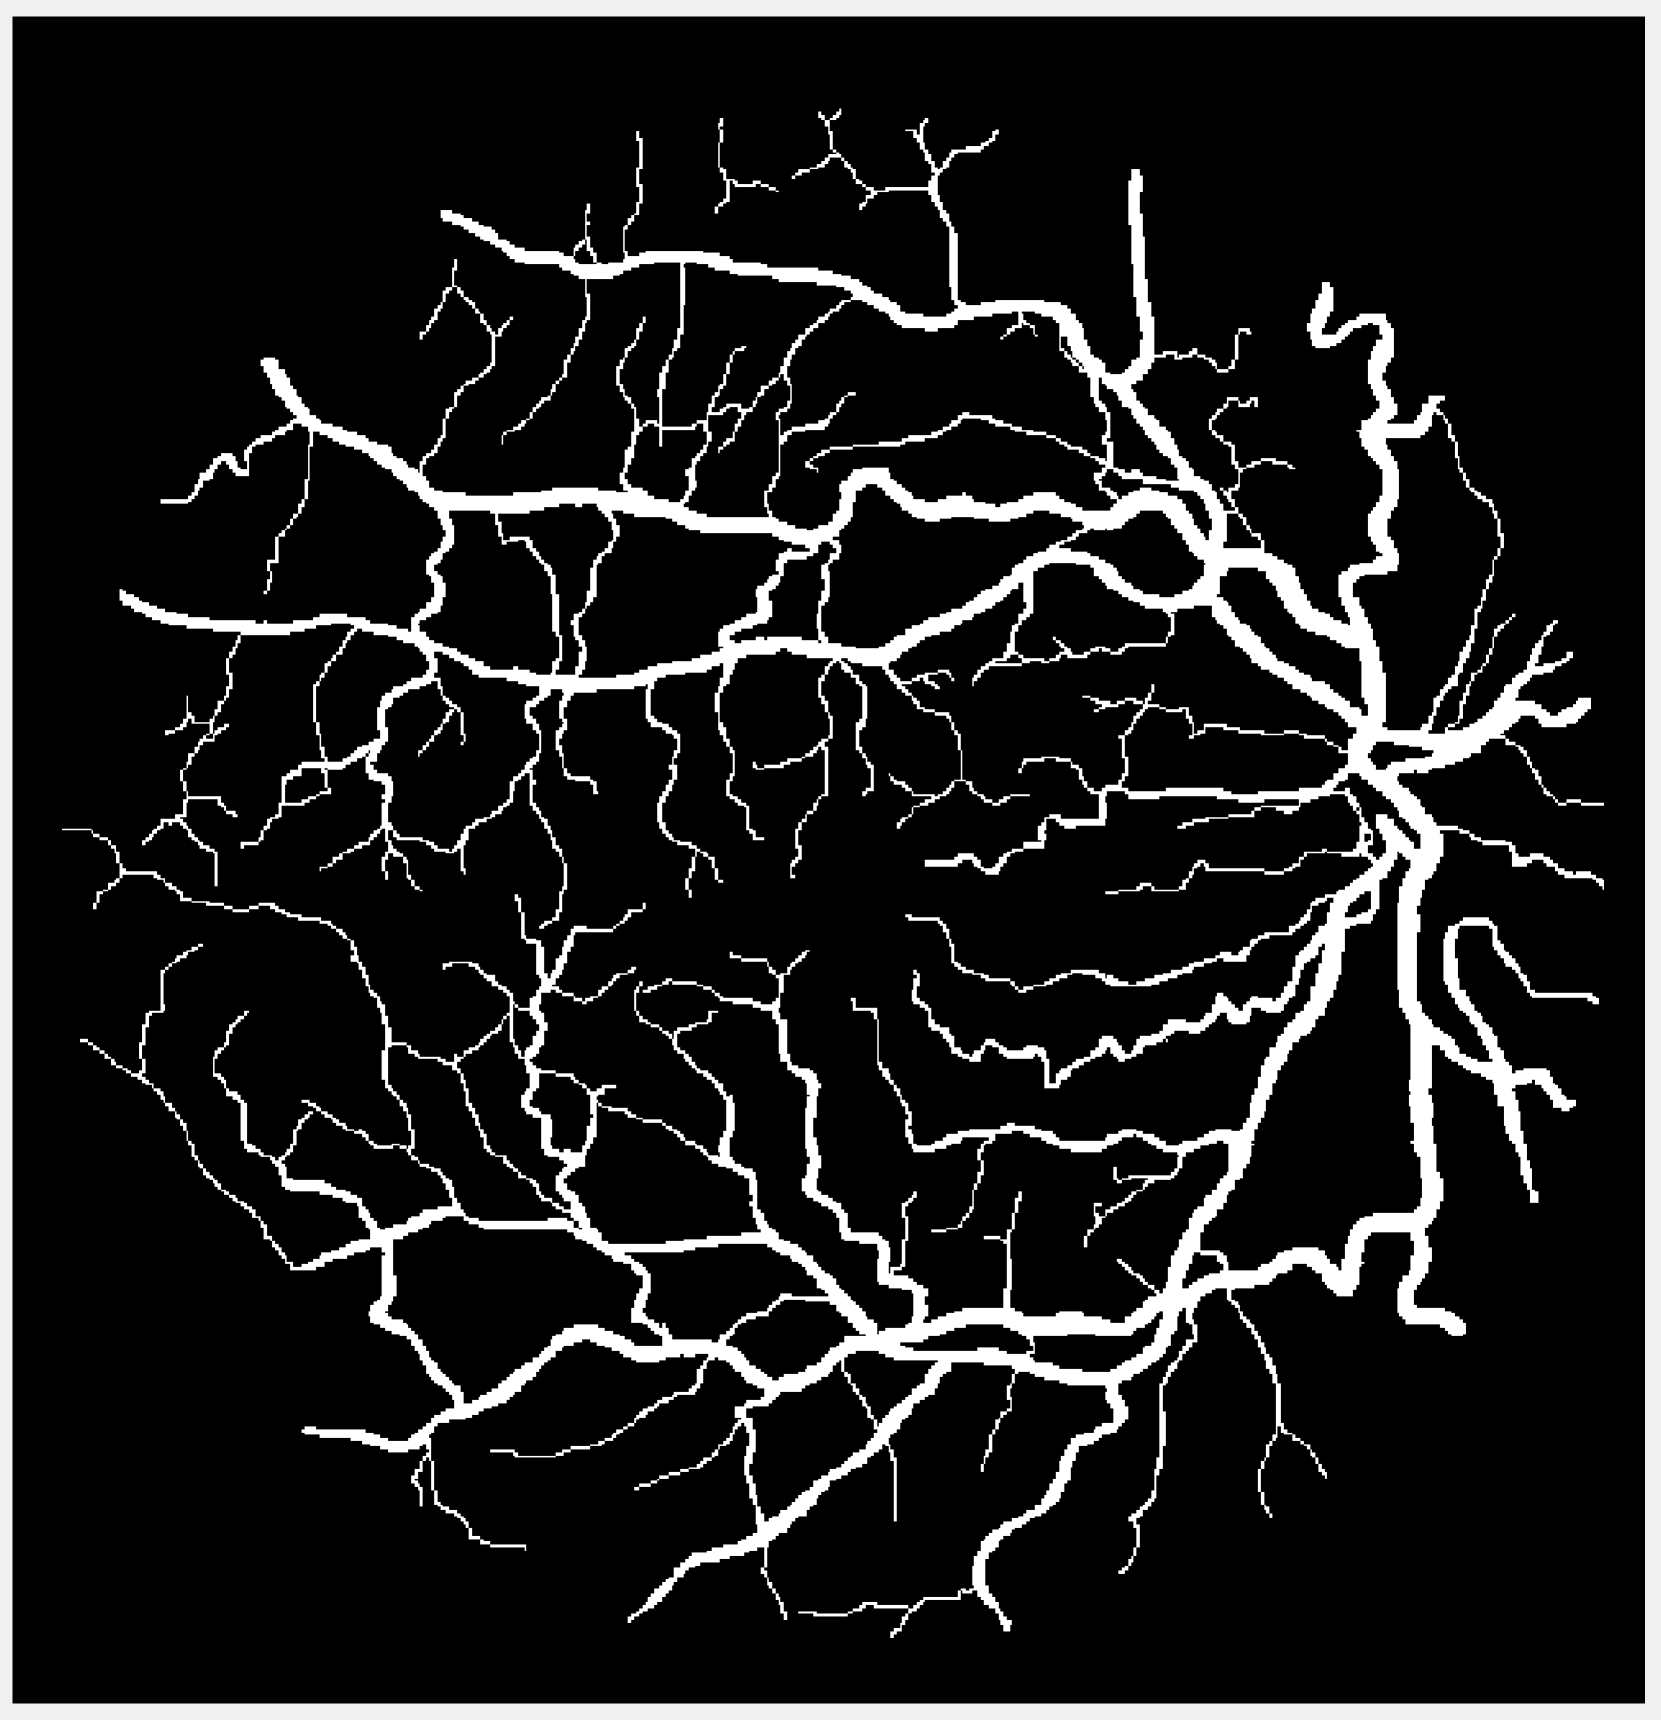

(a) Vessel 1

Figure 1: Original images for testing. (a)-(c) Retinal vessel images from the DRIVE dataset [23]. Image size is 584×565584565584\times 565584 × 565 with pixel intensities 191 (vessel) and 104 (background). (d)-(g) Brain images from the BrainWeb dataset [24]. Image size is 104×8710487104\times 87104 × 87 with pixel intensities 10 (background), 48 (cerebrospinal fluid), 106 (grey matter), and 154 (white matter).